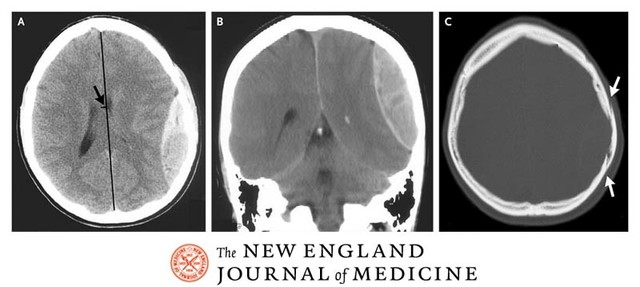

Al examen físico se evidencia la presencia de un trauma contuso en región parietal derecha con la presencia de una fractura deprimida de un espesor mayor al del grosor del cráneo (desplazada). ; además evidencia escoriaciones múltiples sin importancia y una posible fractura de brazo derecho. El resto de la valoración osteomuscular no evidencia traumatismos severos.

Al ingreso al hospital capitalino (4 horas después del accidente), persiste con un Glasgow menor de 9, y el TAC reporta la presencia de una fractura en región parietal derecha con la consecuente formación de un hematoma epidural grande, en la valoración neurológica se apreció la presencia de pupila dilatada y fija del lado derecho que corrobora la presencia del hematoma.